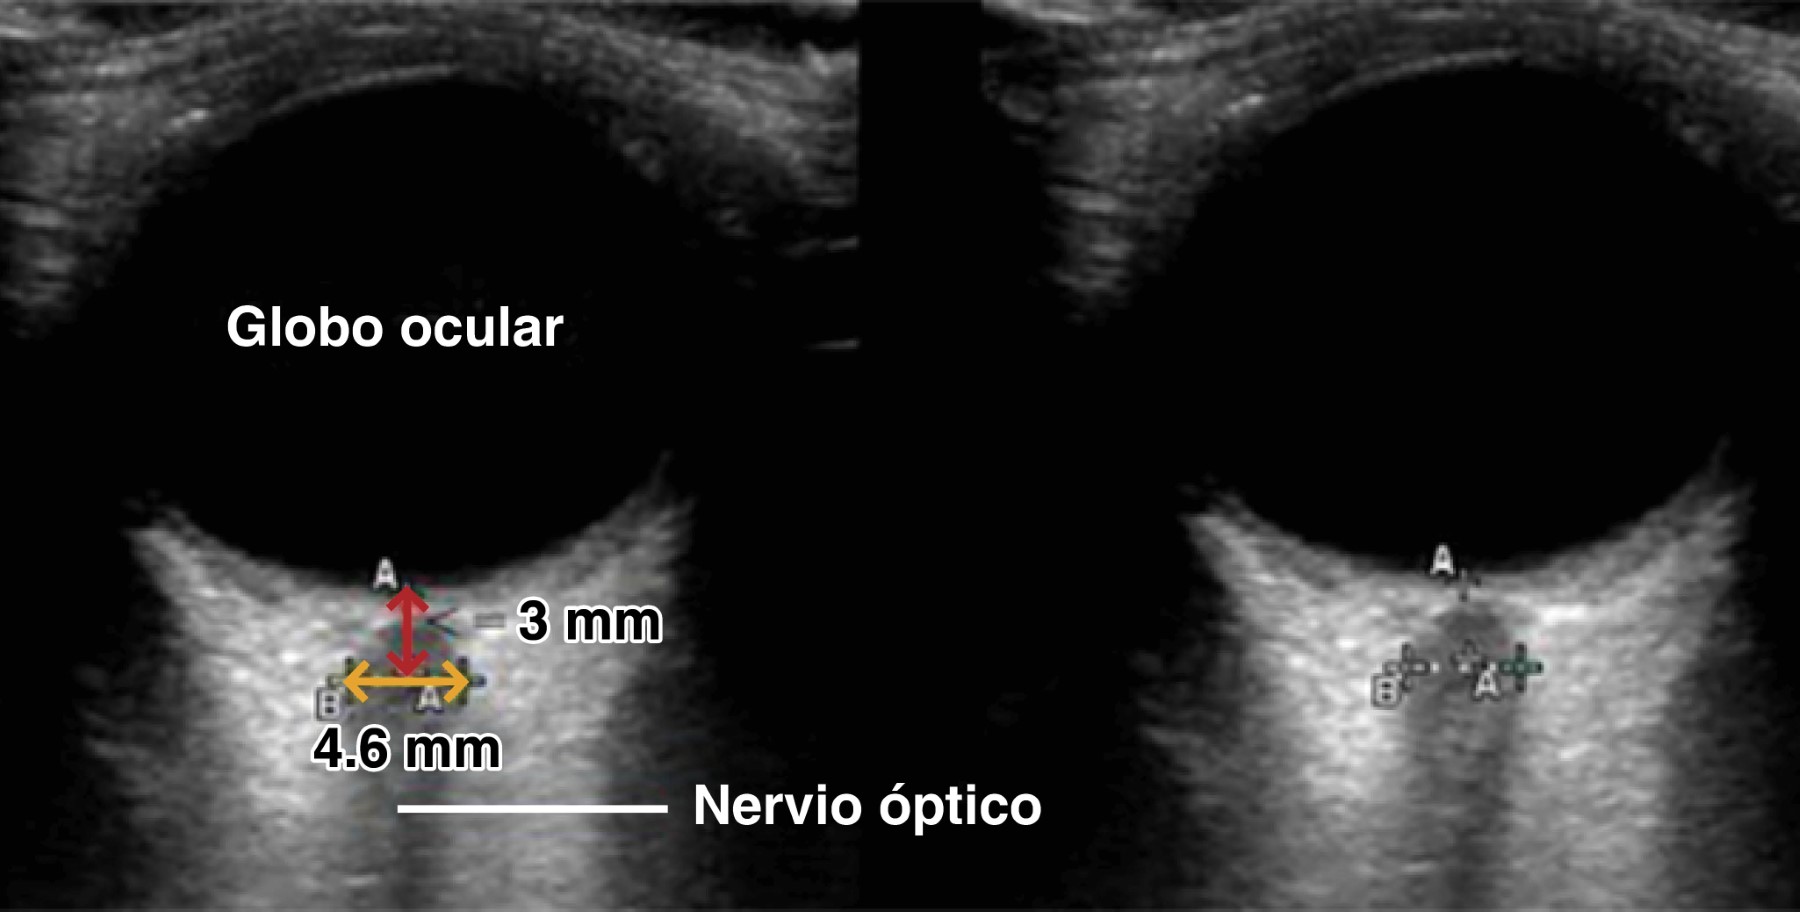

La técnica para identificar la vaina del nervio óptico se realiza con un transductor lineal sobre el ojo cerrado, con el paciente en posición supina, el transductor debe ir en el eje axial.12 El nervio óptico es identificado como dos líneas hiperecoicas detrás del ojo. Se mide 3 mm detrás de la papila, detrás de la línea hiperecoica, usando la función de los calipers en la máquina de ultrasonido; posteriormente se traza una línea entre los limites externos de las líneas hiperecoicas detrás del globo. El valor normal descrito es 4.6 mm. Las mediciones deben realizarse en ambos ojos, debido a la existencia de papiledemas unilaterales y dilataciones asimétricas de las vainas perineurales3 (Figura 3).

La técnica para usar el modo B y la medición de la vaina del nervio óptico fue descrita en 1993 por Hansen y asociados.12 Más adelante, con estudios en cadáveres, se concluyó que el lugar para encontrar la mayor distensión del nervio óptico se ubica a 3 mm detrás del globo ocular; esta localización es, desde entonces, el estándar para realizar las mediciones.